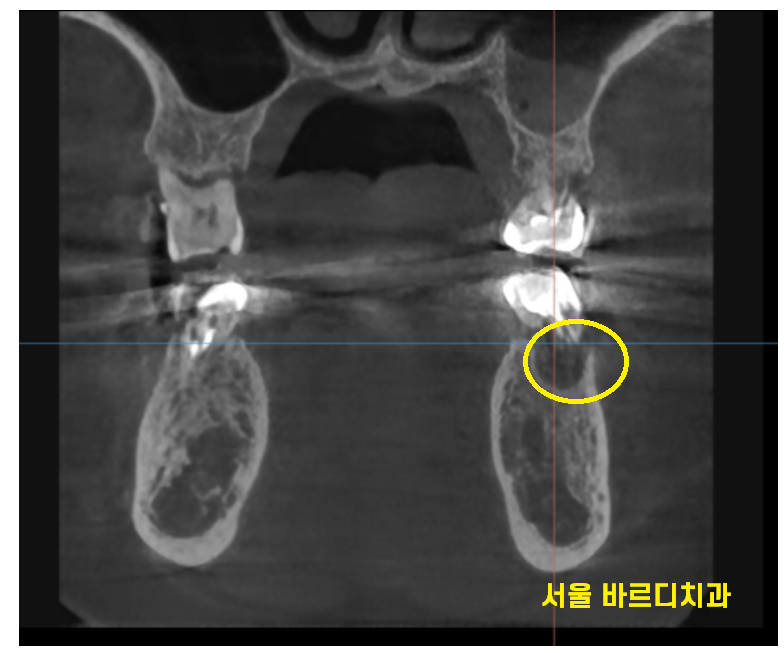

그중에서도 왼쪽 맨 끝에 치아가 심각했습니다.

뿌리를 감싸고 있는 뼈가

까맣게 보이네요~

염증으로 많이 녹기도 하였고

어금니 흔들림을 동반한 통증

느끼실만큼 많이 상하였습니다.